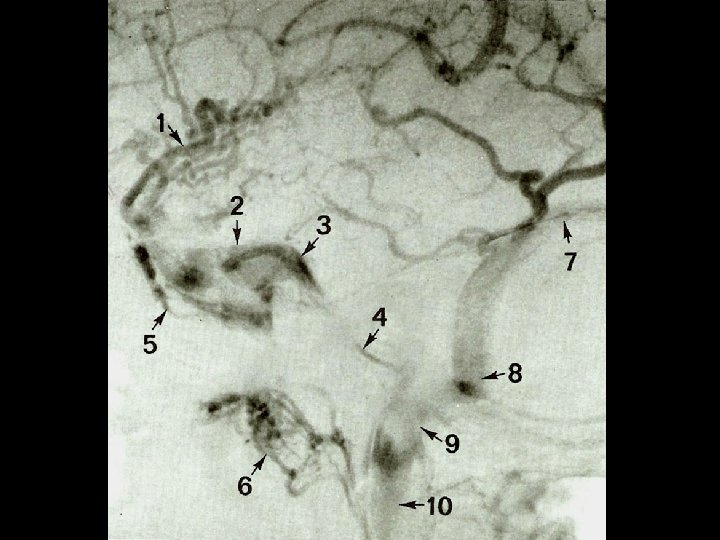

Superficial Veins • Sylvian vein • Vein of Trolard • Vein of Labbe • Cortical veins draining into the dural sinuses Michigan Neurosurgery